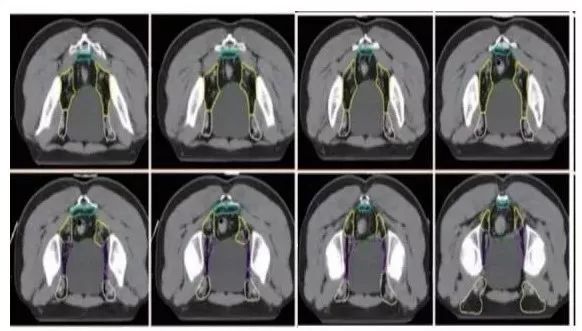

a. 骶前区:骶骨前方区域,包括腹部骶前区⁃PS S (青色) 和盆腔骶前区⁃PS (淡蓝色)(2B 级证据);

b. 直肠系膜区:由全部直肠系膜区以及直肠系膜筋膜组成⁃M(深绿) ;

c. 髂内淋巴引流区⁃LLN P (黄色);

d. 闭孔淋巴引流区⁃LLN A (紫色);

e. 髂外淋巴引流区⁃EI (灰白色);

f. 腹股沟淋巴引流区⁃IN (黄褐色);

g. 坐骨直肠窝⁃IRF (天蓝色);

h. 肛门括约肌复合体⁃SC (桔色)

(b⁃h:1 级证据)。

高危淋巴结引流区及高危复发区边界定义及图谱(CT层厚0.5cm,俯卧位)

勾画图谱